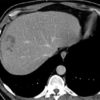

Sán lá gan

» Thông tin: Nam giới – 52 tuổi.

» Lâm sàng: Kiểm tra sức khỏe.